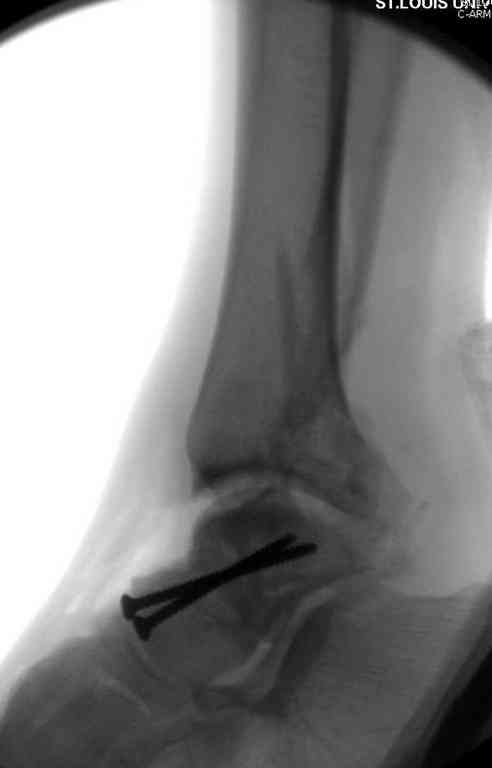

10 дней назад поступил с открытым повреждением медиальной лодыжки и переломо вывихом таранной кости. Ургентно сделана репозиция с наложением наружного фиксатора + Irrigation&Debridment.

Во время репозиции выявили повреждение заднего сухожилия м. тибиалис и задней большеберцовой артерии. Медиальную рану удалось закрыть частично и установлен вакуум.

Дважды провели Irrigation&Debridment с заменой вакуума.